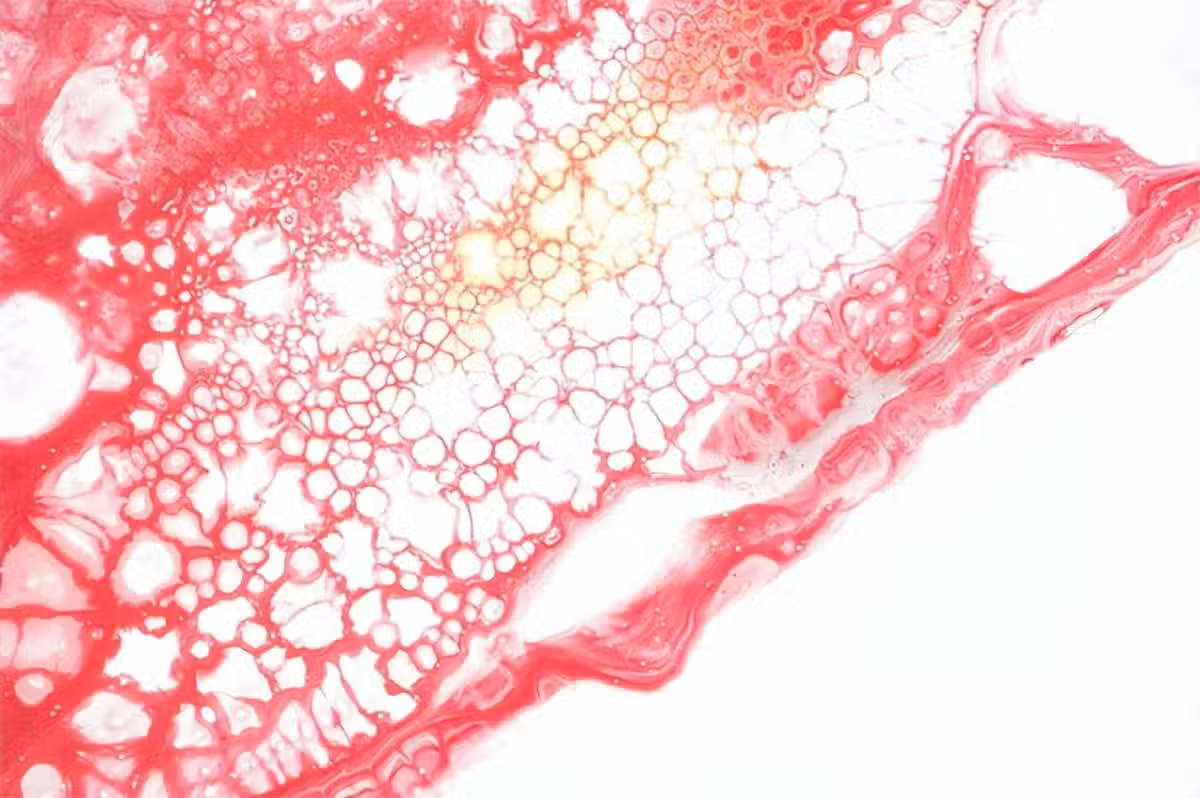

脂肪細胞的三個主要功能,脂質存儲、內分泌功能和對胰島素的反應性,任何一個受到限制都會對人體整體的代謝平衡產生巨大影響。而我們上文已經介紹,大腦作為一種高度代謝的器官,特別容易受到外周代謝的影響,其中就包括由脂肪組織功能障礙引起的變化。

第一點就是脂肪組織引起的肥胖會顯著增加腦梗的發生機率。

目前有廣泛研究已經證實,肥胖是腦梗重要的危險因子之一,大腦內部脂肪的增多會加重主動脈的堵塞情況,從而增加腦梗發生機率。而且脂肪的過度攝入會導致心外膜脂肪組織的厚度增加,而有研究表明,心外膜脂肪組織的厚度增加會增加腦梗發作的風險。